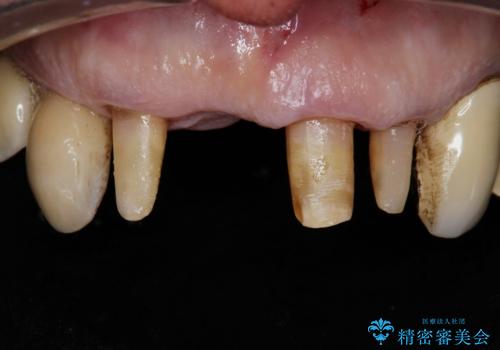

前歯がグラグラする。

- 前歯がグラグラするとの事で来院。

精査したところ、右上の前歯はかなり動揺があり保存できない状態でした。